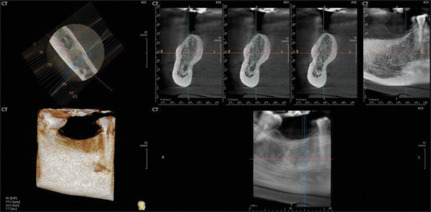

Materials and methods: Hard- and soft-tissue changes were evaluated in both the groups. Evaluation of crestal bone loss (CBL) with cone beam computed tomography and SBI, PD and PESs were evaluated by various indices at 2, 4, and 6 months postloading.

Results: The mean CBL in the Ti abutment is higher; the difference between the two groups was not statistically significant. SBI and PD for Zr were higher, but there was no statistically significant difference between the two groups. Zr had a higher PES than Ti abutment and the difference between the two groups was statistically significant. In the literature till date, the PES of Zr abutments were proven better for provisional restorations in implant prosthesis, but very few literatures support the same for the final implant restorations.